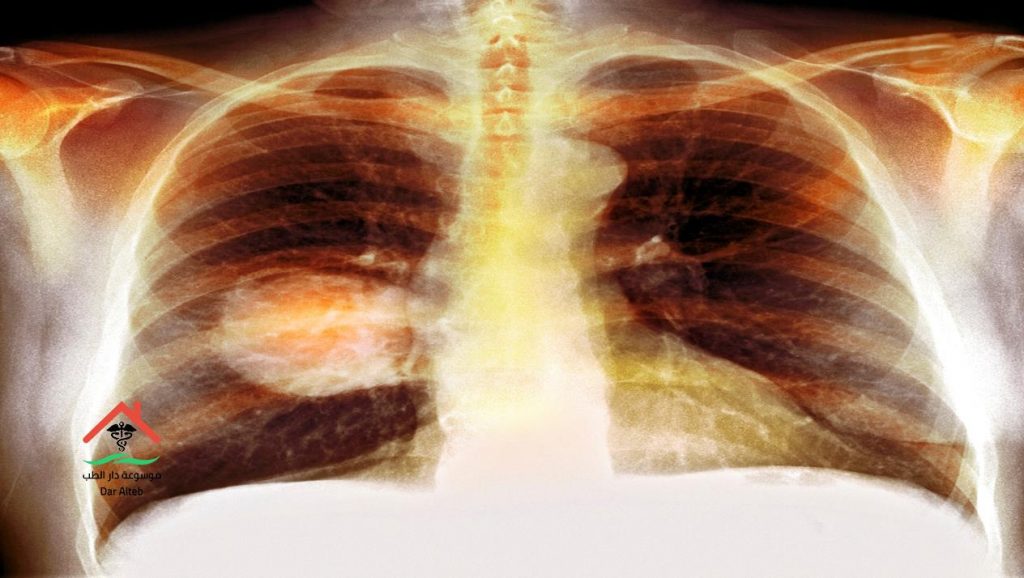

اعراض سرطان الرئة وطرق علاجه والوقاية منه معلومات هامة

اعراض سرطان الرئة وطرق علاجه هو عبارة عن إختراق للرئتين من الخلايا السرطانية التي تنتشر مع الوقت في الجسم إذا لم يتم العلاج، وتعتبر الرئتين من أهم الأعضاء والمسؤولة عن إيصال الأكسجين الضروري لجريان الدم وإخراج ثاني أكسيد الكربون، وحينما تصاب الرئة بالسرطان تحدث إعاقة لوظائفها فلا تعمل بصورة صحيحة وتتكاثر الأورام بها فتنتشر في الأوعية الدموية، ومن خلال هذا المقال سوف نتعرف على أعراض سرطان الرئة وكيفية علاجه.

تشخيص مرض سرطان الرئة

إن الأطباء حتى الأن غير متأكدين مما إذا كان إجراء فحوصات المسح للكشف عن سرطان الرئة ضروري أم لا، ولكن من أهم الفحوصات التي يتم من خلالها تشخيص المرض ما يلي: